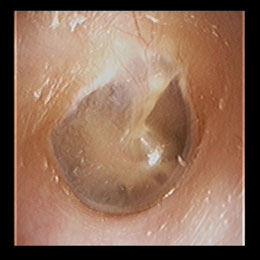

正常な右鼓膜

当院における内視鏡診療の中核をなすのがこの電子ファイバースコープです。 鼓膜や鼻の奥、のどの観察は耳鼻咽喉科にとって欠かせないものですが、当院では原則として鼓膜の観察は、この電子ファイバースコープを用いておこなっています。 ファイバーと呼ばれるだけあって、柔らかい素材でできており、細く曲がったところもスルスルと通り抜けて目的の場所をくっきりと映し出してくれます。 耳の中(外耳道)や鼻の中がまっすぐな人はいません。電子ファイバースコープはクネクネ曲がりますので、耳、鼻、のどの観察にもってこいです。当院の電子ファイバースコープは直径2.6mmと世界でも細径クラスです。

電子ファイバースコープを用いることによって「裸眼もより正確な診断ができる」ことと、患者様にも鼓膜の状態をご覧いただけて、その画像を時系列で保存し閲覧ができるため、患部の状態の経過(良くなってきているのか、悪化しているのか?)が一目瞭然でご確認いただけます。